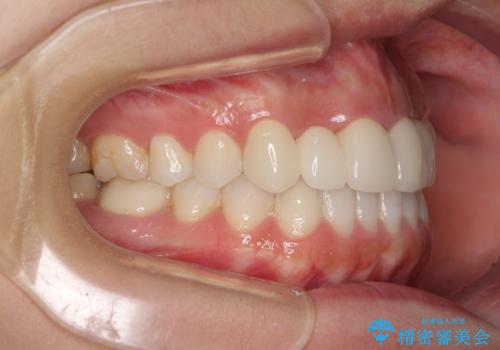

- 審美的ではない上の前歯とデコボコの下の前歯、歯茎が腫れている奥歯を気にして来院された患者様です。

根管治療の必要な歯がいくつかあるため、まずは根管治療を行い、その後インビザラインにて矯正治療を行うこととしました。

矯正治療後に前歯をセラミックブリッジに、奥の銀歯はセラミックインレーやPGAインレー(ゴールドインレー)にて補綴・修復治療を行うこととしました。

矯正治療により下顎前歯を整列させたため、上顎前歯のセラミックブリッジを補綴することで口元を少し下げることができました。

ヒトの目線がいつも口元に向けられているように感じることがなくなり、患者様には大変満足していただきました。